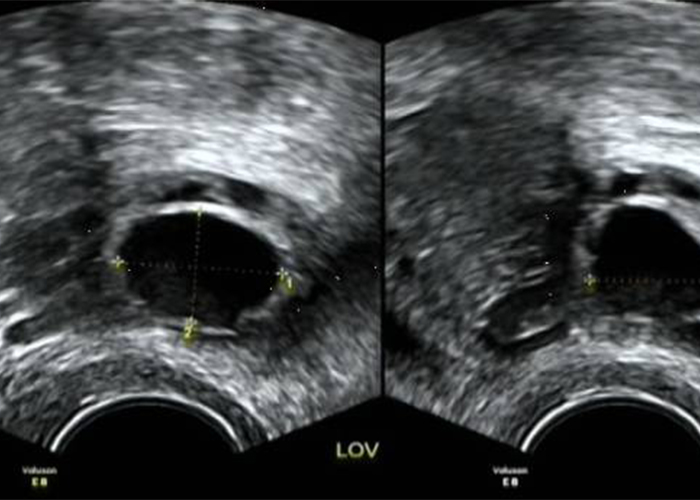

3、卵泡的监测

卵泡监测一般从月经周期的第3-5天开始!

月经3-5天:观察窦状卵泡数量

月经9-12天:常规开始监测卵泡,隔2-3天监测

卵泡>15 mm时:每天或隔天监测

卵泡>18 mm时:为成熟卵泡,此时可诱导排卵

整个月经周期,卵泡的生长速度是不一致的:

初期(月经1-10天)为1.2 mm/d;

后期(月经5天-排卵前)平均为1.5 mm/d;

排卵前4天生长速度最快,为2 mm/d。

排卵监测也会遇到一些问题,比如多囊卵泡、卵泡囊肿、黄体囊肿等,这时就需要进一步就诊检查。

多囊卵泡:正常育龄期妇女有3-11个卵泡,当超声发现一侧或双侧卵巢直径2-9 mm的卵泡个数大于等于12个时,需要进一步检查,排除多囊卵巢综合征的可能。

卵泡囊肿:当卵泡直径大于25 mm而不排卵时,可以定义为卵泡囊肿,一般2-3个月经周期后自然消退,甚至时间更长,不需特殊处理。

黄体囊肿:由于出血量和时间的差异,黄体可以表现为囊性、混合性和实性,未孕女性一般2个月经周期内消失,妊娠女性存在时间稍长,一般也会自然消失。

小卵泡或无卵泡:当育龄期妇女卵巢较小,内部无明显卵泡或持续存在极小卵泡时,需要进一步检查妇科内分泌,排除卵巢早衰的可能。